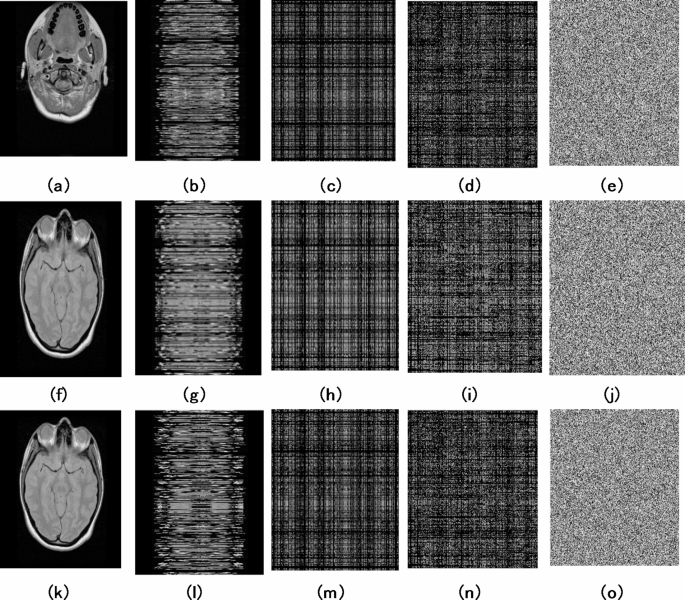

This section discusses the efficiency and sternness of the proposed medical image encryption algorithm against various attacks. Figure 6 shows the three-sample test DICOM images and the corresponding images after row shuffling, column shuffling, selective shuffling and inter & intra- pixel diffusion processes. From Fig. 6, it can be viewed that the pixels of the images are effectively scrambled and diffused. Further, various tests with the corresponding numerical results are presented and tabulated in this section to demonstrate the effectiveness of the proposed algorithm.

Encryption test image results: (a) Test image 1, (b) Row-wise shuffled image 1, (c) Column-wise shuffled image 1, (d) Selective shuffled image 1, (e) final diffused image 1. (f) Test image 2, (g) Row-wise shuffled image 2, (h) Column-wise shuffled image 2, (i) Selective shuffled image 2, (j) final diffused image 2, (k) Test image 3, (l) Row-wise shuffled image 3, (m) Column-wise shuffled image 3, (n) Selective shuffled image 3, (o) final diffused image 3.